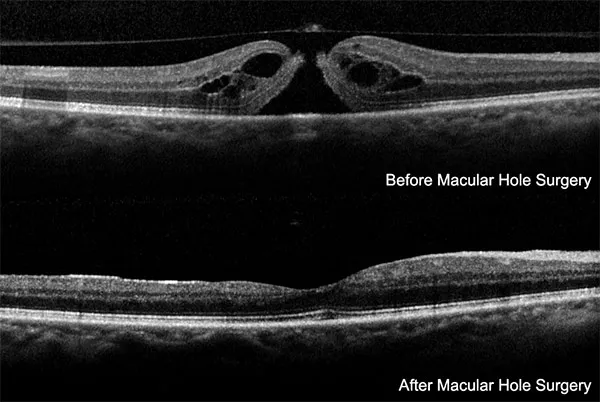

- Macular Hole Surgery:

- PPV + ILM peel + gas. High success.

⭐ ILM peeling in macular hole surgery boosts anatomical closure (>90%) & vision.